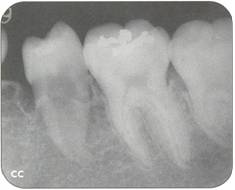

Fi 545e45f g 5-1d Preoperative periapical radiograph. |

Fi 545e45f g 5-1a Preoperative panoramic view. The patient is a 24-year-old female. Transplantation of the mandibular right third molar to the area of nonrestorable mandibular first molar is planned. |